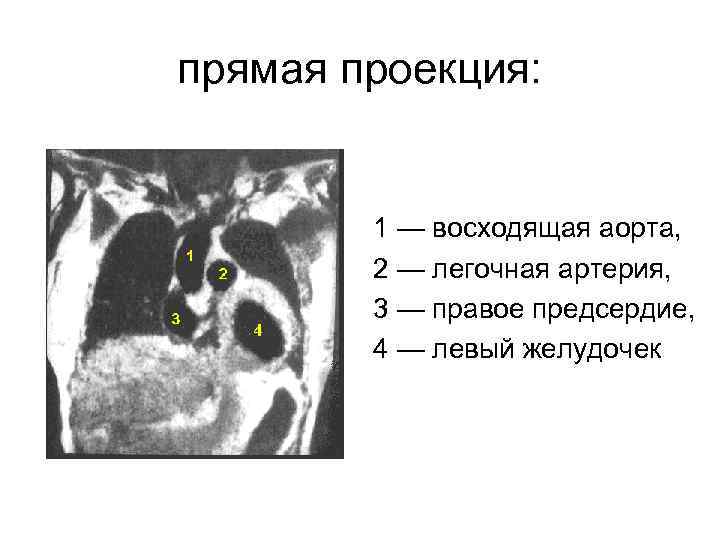

прямая проекция: 1 — восходящая аорта, 2 — легочная артерия, 3 — правое предсердие, 4 — левый желудочек